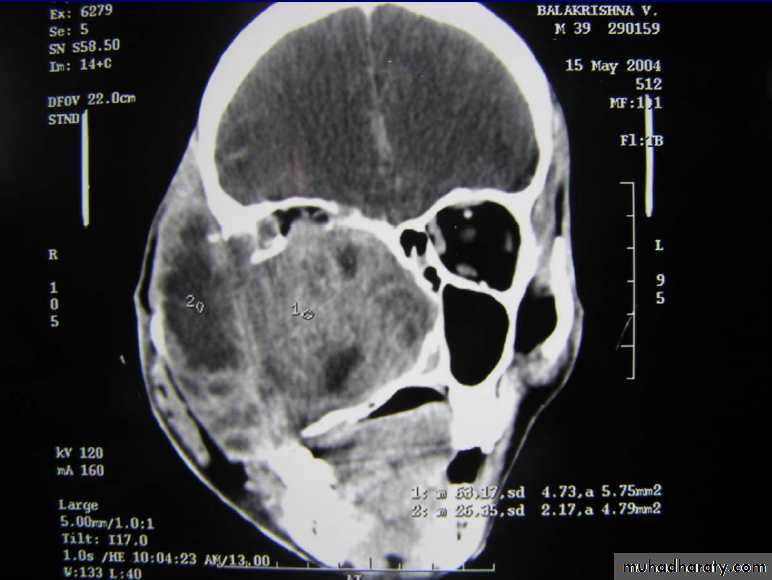

DIAGNOSIS:X-ray PNS.

CT Scan of PNS ( Coronal & Axial).

CA MAXILLARY SINUS

Arises from the lining of max sinus.• Middle aged males(40 -60yrs)

Remain silent for a long time or showing only symptons of sinusitis

Late :destroy bony walls & invades in to surrounding structures.